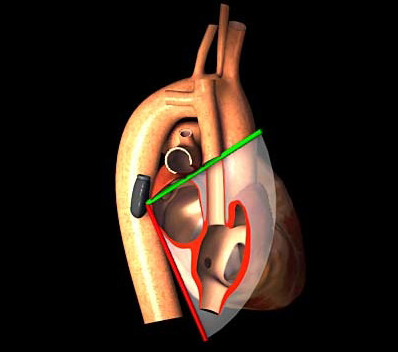

As its name suggests, the bicaval view allows you to see both vena cava - IVC and SVC - in one shot. It's obtained by placing the probe into the mid-esophagus, and rotating the omniplane angle to 90 degrees. Incredible simulator here: pie.med.utoronto.ca/tee/TEE_conten… (4/8)

But it can also be seen as a bi*atrial* view because it allows you to see the RA and LA in one shot as well - including, of course, the interatrial septum. Note that the septum has two "beefy" ends, with a thin filament-appearing layer connecting them - the septum primum. (6/8)

Normally, at birth, this adheres to the thicker septum secundum. Sometimes it doesn't truly seal, but the higher pressure of the LA (above the RA) keeps it flush against the septum secundum and closed. But when RA pressure rises above LA pressure, the flap can open ➡️PFO (7/8)